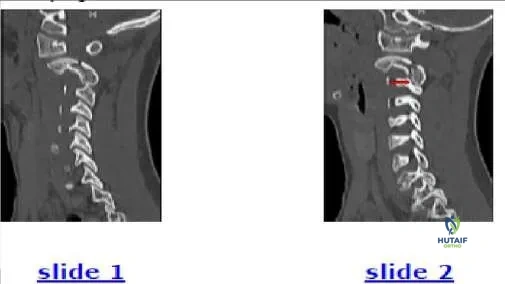

A 12-year-old boy presents for evaluation of a spinal curvature (Slide 1). Which of the following is the most likely cause of the spinal curve:

Correct Answer: Limb length inequality

This patient has a 2.5 cm shortening of the left lower extremity, which can be seen from the uneven pelvic height on the radiograph. The shortening produces a compensatory curve. No rotation is present within the curve. Scanogam (Slide 2) documents the inequality. When the patient stands on a 2.5-cm lift, the curve is eliminated (Slide 3).